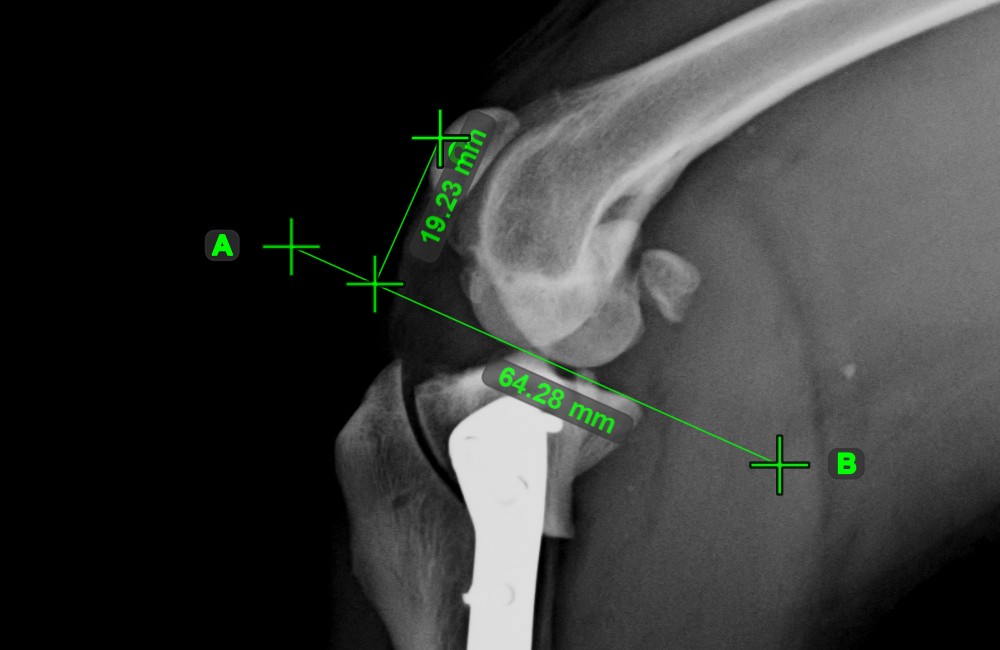

Line Measurement¶

Select the Line Measurement

tool and assign it to one of the available mouse buttons. Place the start and end points on the scene or select them from already existing points on the image. The distance between the two points will be automatically

calculated by using the default calibration data, or the recalibrated data by the length calibration measurement.

Modify the start and end point by using the Select/Move Item

tool. The distance between the two points will be automatically recalculated.